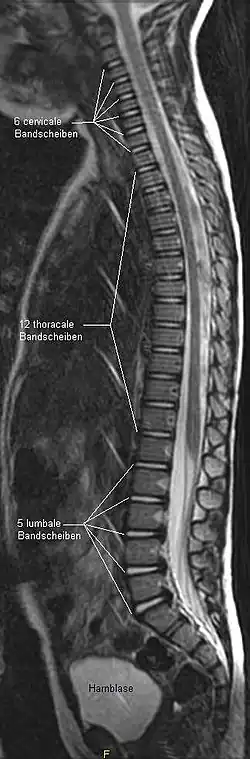

Von oben (kranial) nach unten (kaudal) wird die Wirbelsäule in fünf einzelne Abschnitte (Wirbelsäulensegmente) unterteilt, die sich jeweils aus einzelnen Wirbeln (lat. Vertebrae) zusammensetzen. Beim Menschen sind dies die Halswirbelsäule (Pars cervicalis) mit sieben Wirbeln, die Brustwirbelsäule (Pars thoracica) mit zwölf Wirbeln, die Lendenwirbelsäule (Pars lumbalis) mit fünf Wirbeln, das Kreuzbein (Os sacrum) mit fünf durch Synostose verschmolzenen Wirbeln und das Steißbein (Os coccygis) mit vier bis fünf verschmolzenen Wirbelrudimenten (individuell und je nach Alter). Die menschliche Wirbelsäule besteht demnach aus insgesamt 33 oder 34 Wirbeln. Da die fünf Wirbel, die das Kreuzbein bilden, ebenso wie die Wirbelrudimente des Steißbeins miteinander verwachsen (verschmolzen) sind, spricht man auch oft davon, dass die Wirbelsäule aus 24 freien (präsakralen) Wirbeln (Hals-, Brust- und Lendenwirbelsäule) sowie dem Kreuzbein und dem Steißbein besteht.